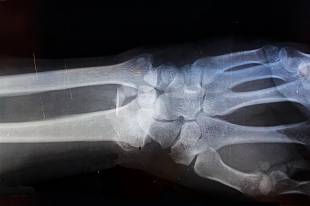

이러한 상태는 X-ray에서 아주 얇은 금처럼 보일 때가 많으며, 부기가 서서히 증가하면서 해당 부위에 열감이 퍼집니다. 환자는 이를 단순 타박상으로 생각하기 쉬우나, 압력을 가할 때 내부에서 당김과 쿡쿡 찌르는 느낌이 반복되는 경우 골절의 가능성이 높습니다. 특히 손가락이나 발가락처럼 작은 뼈는 미세 골절이 있어도 움직임이 제한되지 않는 것처럼 보여 오해하기 쉽습니다.